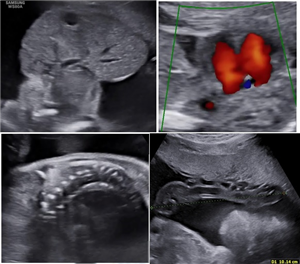

CLS: Xuất huyết tiểu não ở thai nhi